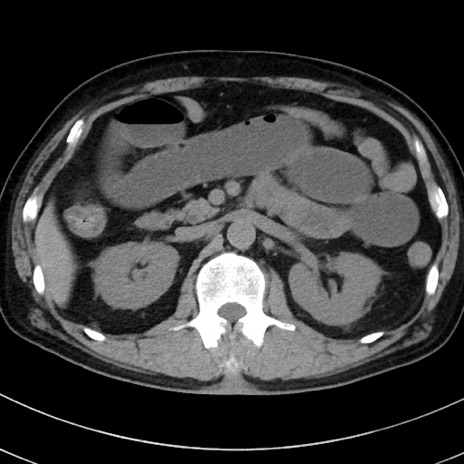

症例38(横断像)

【症例】70歳代 男性

【主訴】腹痛・嘔吐

【現病歴】昨晩より、嘔吐・腹痛あり。今朝になっても嘔吐あり。来院。

【既往歴】心臓バイパス手術、開腹胆摘、腸閉塞

【身体所見】BP 107/71mmHg、HR 116/min、腹部:平坦、軟、下腹部に軽度圧痛あり。反跳痛なし。

【データ】WBC 15100、CRP 0.32